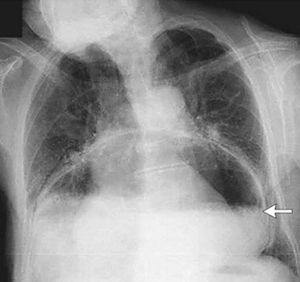

Nope in ascites x ray shows full air in whole abdomen while here it shows there is no air in uper part i mean near to diaphragm

Nope pnuemonia contain air in most of the lobes of any side of lung or both side of lung .. while here its changing postion of diaphragm or esophagus (hint for the ans )